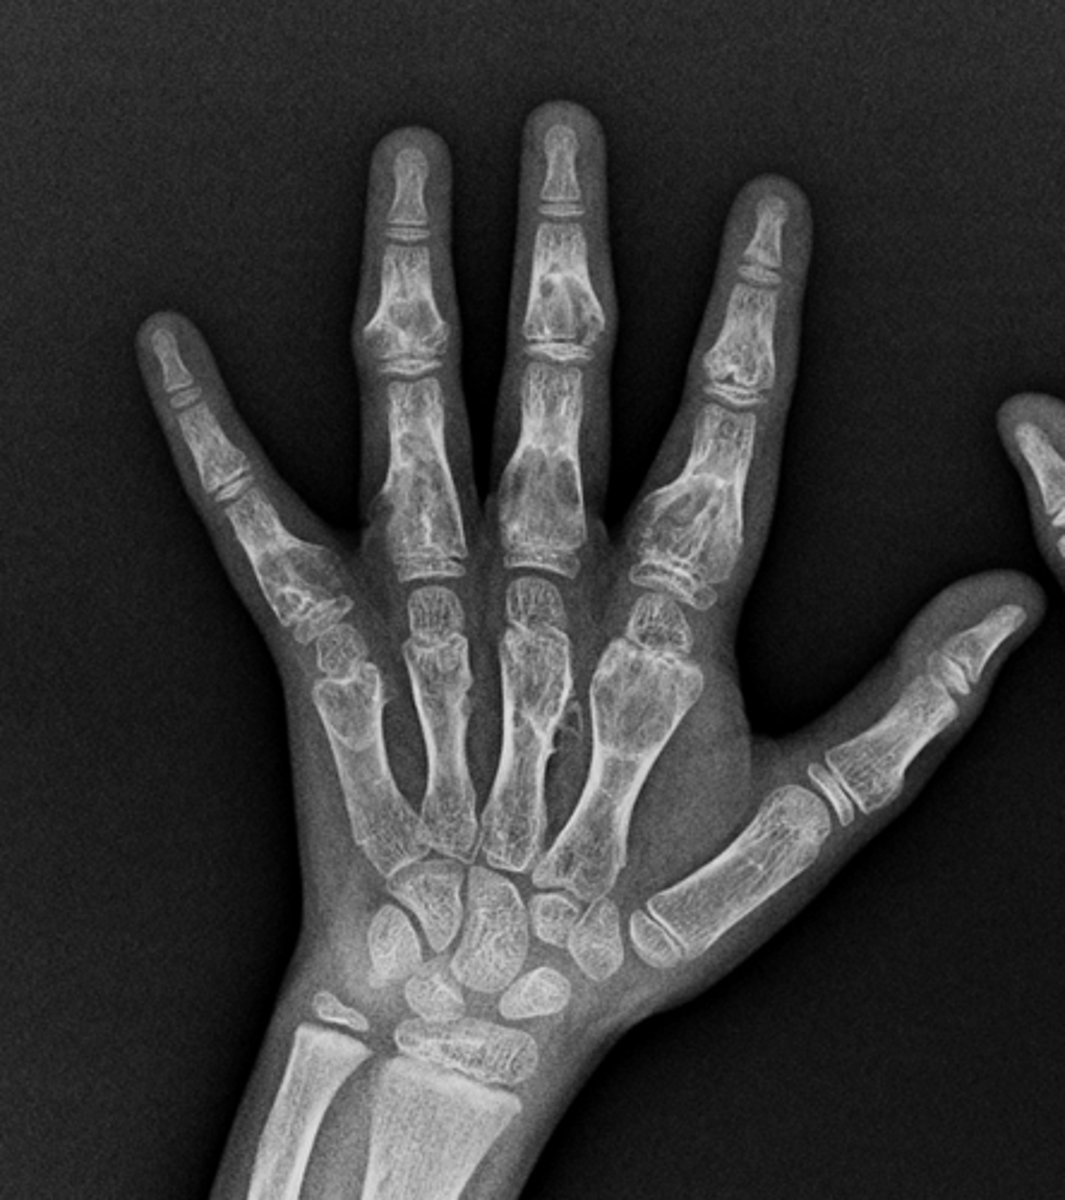

- Head of 5th metacarpal

• Cortical thinning

• Lucency in head

• Pathologic fracture

• Stippled calcification

• Cartilaginous matrix

• Geographic

• Short zone of transition

Describe the lesion

<p>Describe the lesion</p>

Solitary enchondroma

Most likely diagnosis?

<p>Most likely diagnosis?</p>

Fracture

What complication has occurred?

<p>What complication has occurred?</p>

Refer to orthopedist

Next step?

<p>Next step?</p>

Multiple enchondromas (Ollier's disease)

Diagnosis?

<p>Diagnosis?</p>

- Malignant transformation (10-50%)

- Fracture

Concerns/complications?

<p>Concerns/complications?</p>